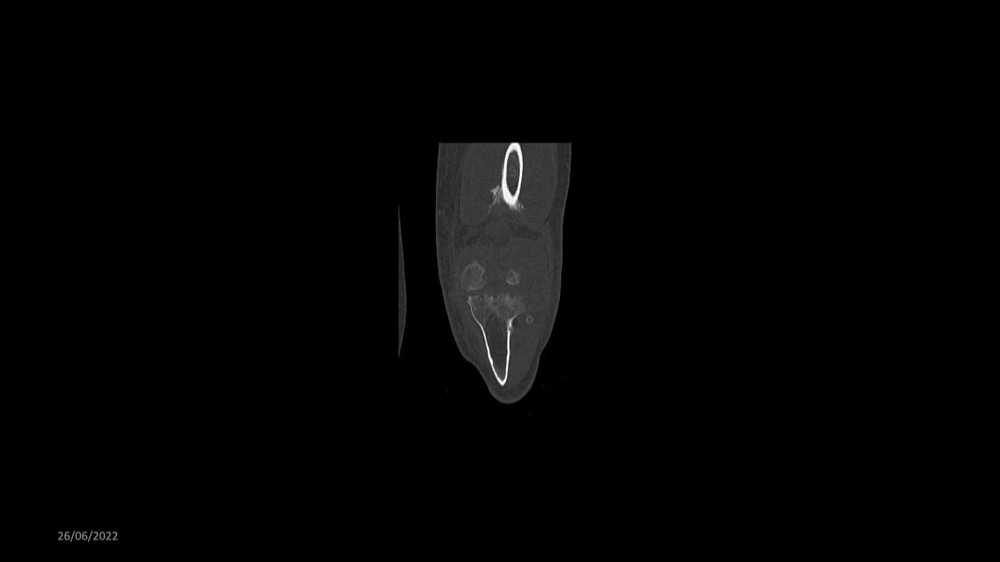

Reichert / Amar / Tordjman / Carlier 29/06/2022